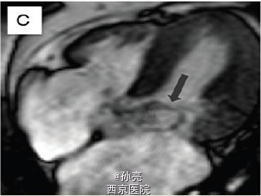

48 岁男性患者,4 年前因梗阻型肥厚性心肌病曾于我院医疗中心行室间隔无水酒精消融术。尽管术后使用β受体阻滞剂、异搏定和丙吡胺,患者仍有劳力性呼吸困难症状出现。 结合既往心脏 CT 片对照,未发现有意义的冠状动脉病变。室间隔壁为 12mm 厚。更进一步,我们观察到收缩期时二尖瓣有一个不同寻常的组织突出于左室流出道(图 1B)。 这种机械方面的梗阻我们再次用经胸壁超声得以证实,当多余的组织靠近室间隔时,该组织与最大收缩期左室流出道的压力阶差为 80mmHg(图 1B)。 心脏 MRI 再次确认出现的二尖瓣附件组织阻塞左室流出道,加速了收缩期的血液流动(图 1C)